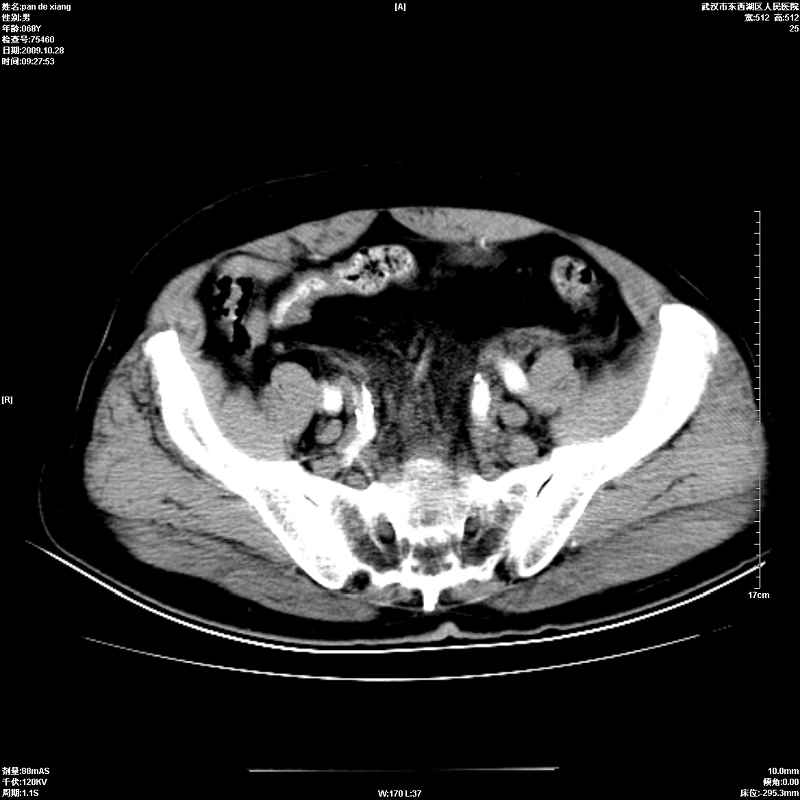

以下是引用杀毒软件在2009-10-28 20:41:00的发言:[br]结合临床考虑---白血病双肾改变或淋巴瘤。

以下是引用zxl51642在2009-10-29 9:59:00的发言:[br]结合临床“单克隆免疫球蛋白血症”,考虑双肾为继发损害并肾功能不全(尿中大量igg及少量iga、igm等大分子免疫球蛋白滤出所致继发损害),椎前软组织肿块为髓外造血。与浆细胞瘤有区别,平扫时有战友说的很清楚。